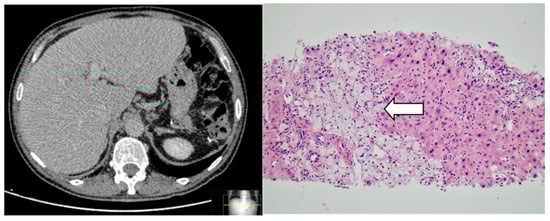

2.1. Clinical Profile